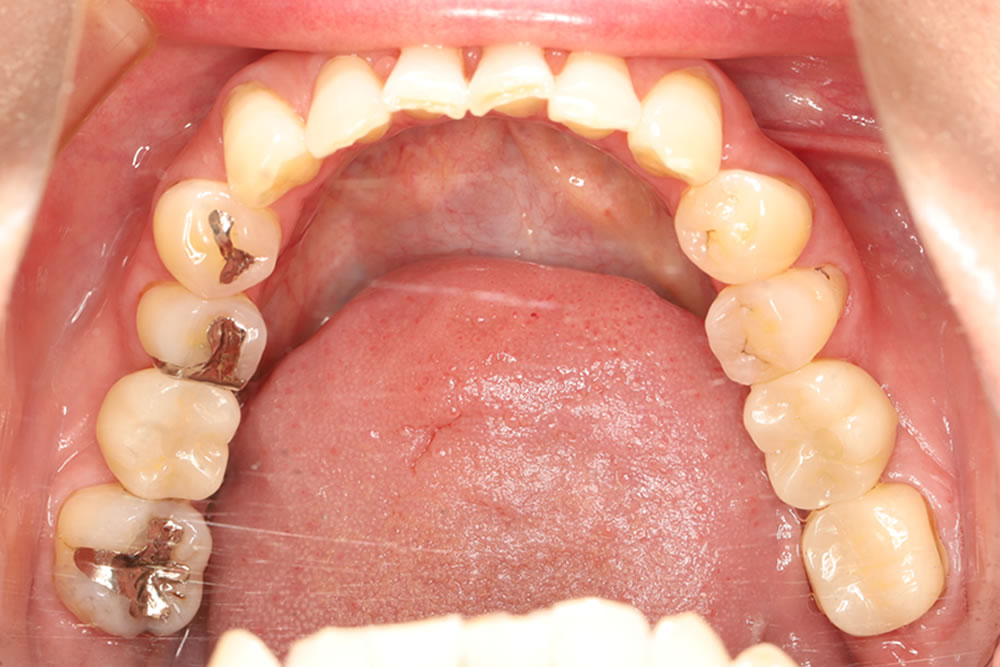

レントゲン上で右下の6番目の根の先端に大きい影が見られます。また左下も噛むと痛みがあるとのことでした。小さい根尖病巣が確認できますが、かなり大きい土台が入っていて再治療が困難な状態なため、患者さまと相談し、右下、左下の大臼歯を抜歯してインプラントで治療する計画を立てました。

治療前後の比較

治療前後の比較画像です。患者さまにも色合い等大変、満足いただけました。